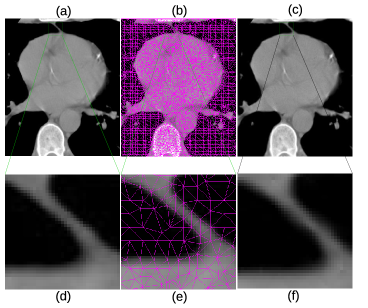

In Fig. 4, more details of the Lena experiment are shown. (a) is the original Lena image, the same as Fig. 3 (a). (b) is the mesh generated by the method outlined in section 2.1. (c) is the recovered image, which is the same as Fig. 3 (e). To visually see the generated mesh and compare the difference between the original and restored images, Fig. 4 (d)–(f) are the zoomed-in views of (a)–(c), respectively. As the results show, the mesh quality is high enough for subsequent numerical analysis and the the recovered image is very close to the original one. As a matter of fact, the restored image looks smoother due to the smooth radial basis functions used, and the sharp edge features are well preserved. Fig. 5 shows the original brain MRI, its generated mesh, and the result of ARBF interpolation using intensities on triangle centers with the MQ basis function. The zoomed-in views show the quality of mesh and restoration as well. Fig. 6 shows another MRI experiment of breast. Fig. 7 shows a CT-scanning experiment. From all these examples, one can see the effectiveness of the proposed approaches for image mesh generation and feature-preserving restoration.